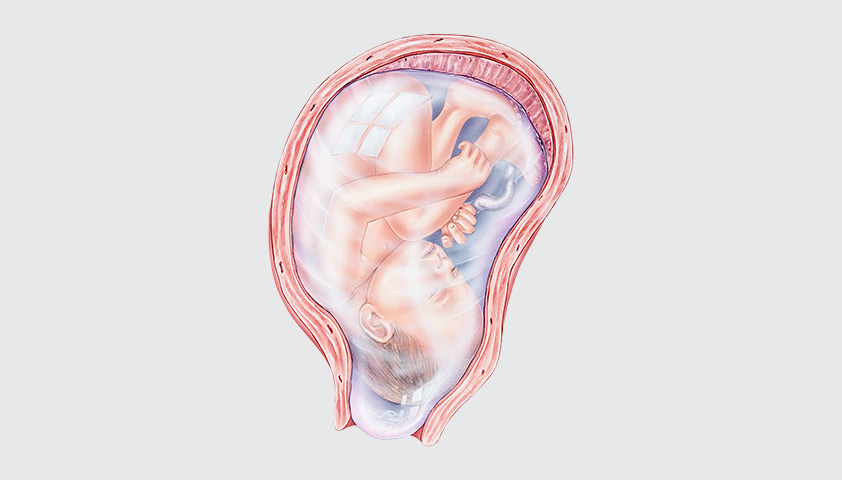

Околоплодный пузырь и плацента: структура и функции